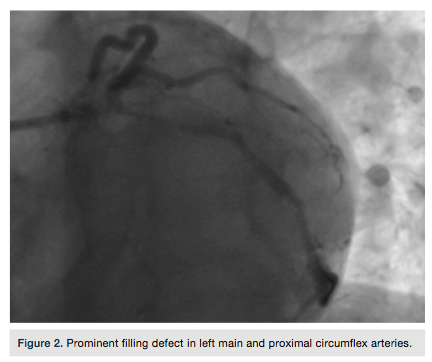

defect in the LMCA and proximal CX artery was encountered that was refractory to nitroglycerin and resembled coronary dissection, due to LMCA trauma from the EBU catheter (Figure 2). The patient had no clinical symptoms or EKG changes. A “pleating artifact” in the LMCA and Cx artery, induced by the stiff structure of the extra support guidewire, was felt to be likely due to the acute angle of the origin of CX artery from the LMCA. The guide wire was partially withdrawn and the filling defect decreased (Figure 3). A stent was appropriately placed into the in-stent restenosis without any complication. The filling defect completely disappeared after complete withdrawal of the guide wire (Figure 4).